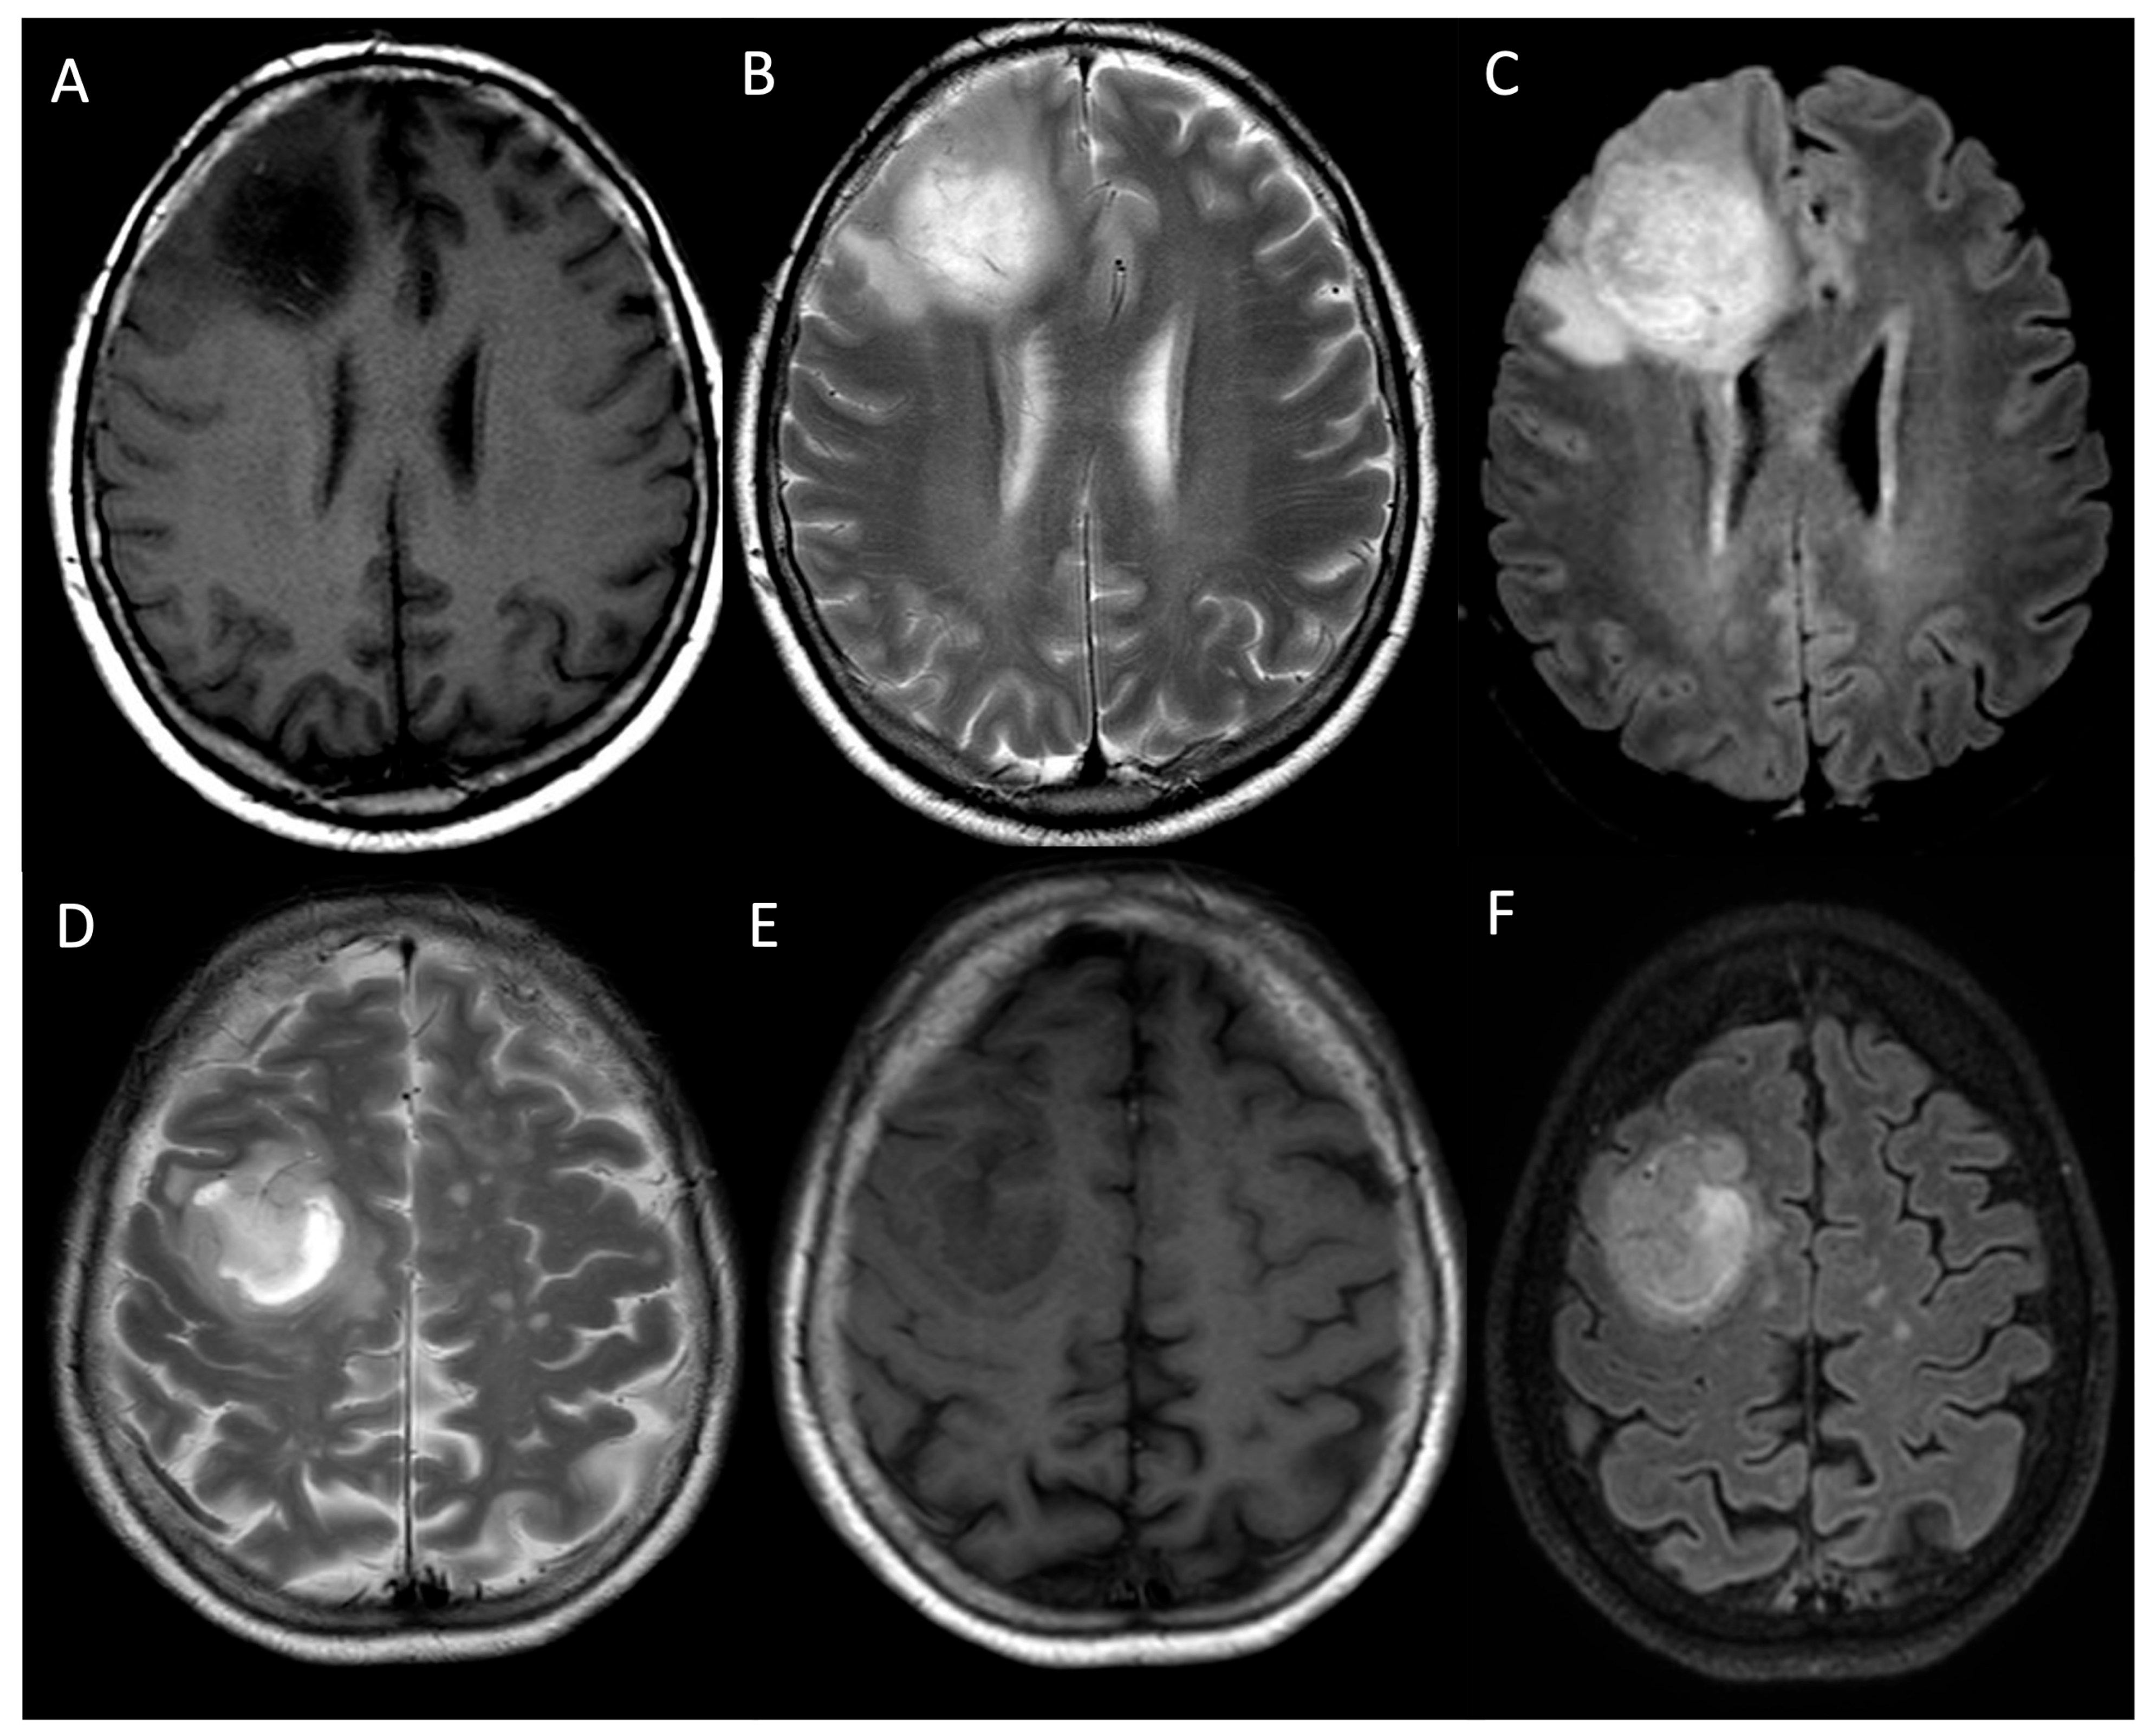

- Bulakbaşı, N.; Paksoy, Y. Advanced Imaging in Adult Diffusely Infiltrating Low-Grade Gliomas. Insights Imaging 2019, 10, 122. [Google Scholar] [CrossRef]

- Smits, M. Imaging of Oligodendroglioma. Br. J. Radiol. 2016, 89, 20150857. [Google Scholar] [CrossRef]

- Smits, M. MRI Biomarkers in Neuro-Oncology. Nat. Rev. Neurol. 2021, 17, 486–500. [Google Scholar] [CrossRef] [PubMed]

- Zulfiqar, M.; Dumrongpisutikul, N.; Intrapiromkul, J.; Yousem, D.M. Detection of Intratumoral Calcification in Oligodendrogliomas by Susceptibility-Weighted MR Imaging. AJNR Am. J. Neuroradiol. 2012, 33, 858–864. [Google Scholar] [CrossRef]

- Kong, L.-W.; Chen, J.; Zhao, H.; Yao, K.; Fang, S.-Y.; Wang, Z.; Wang, Y.-Y.; Li, S.-W. Intratumoral Susceptibility Signals Reflect Biomarker Status in Gliomas. Sci. Rep. 2019, 9, 17080. [Google Scholar] [CrossRef]

- Park, M.J.; Kim, H.S.; Jahng, G.-H.; Ryu, C.-W.; Park, S.M.; Kim, S.Y. Semiquantitative Assessment of Intratumoral Susceptibility Signals Using Non-Contrast-Enhanced High-Field High-Resolution Susceptibility-Weighted Imaging in Patients with Gliomas: Comparison with MR Perfusion Imaging. AJNR Am. J. Neuroradiol. 2009, 30, 1402–1408. [Google Scholar] [CrossRef] [PubMed]

- Grabner, G.; Kiesel, B.; Wöhrer, A.; Millesi, M.; Wurzer, A.; Göd, S.; Mallouhi, A.; Knosp, E.; Marosi, C.; Trattnig, S.; et al. Local Image Variance of 7 Tesla SWI Is a New Technique for Preoperative Characterization of Diffusely Infiltrating Gliomas: Correlation with Tumour Grade and IDH1 Mutational Status. Eur. Radiol. 2017, 27, 1556–1567. [Google Scholar] [CrossRef] [PubMed]